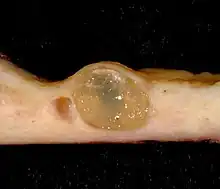

A nabothian cyst (or nabothian follicle)[1] is a mucus-filled cyst on the surface of the cervix. They are most often caused when stratified squamous epithelium of the ectocervix (portion nearest to the vagina) grows over the simple columnar epithelium of the endocervix (portion nearest to the uterus). This tissue growth can block the cervical crypts (subdermal pockets usually 2–10 mm in diameter), trapping cervical mucus inside the crypts.

Nabothian cysts are also incidentally found during MRI imaging. During the healing process of chronic cervicitis, squamous epithelium of ectocervix proliferates and enter the cervical canal (endocervix), covering and obstructing the columnar epithelium of endocervical glands. Thus, retention of mucus in the endocervical glands causes cyst formation. The size of the cyst may vary from a few millimetres to 4 cm in diameter.[3]